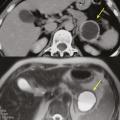

Cystadénome séreux

Il s’agit d’une tumeur kystique multiloculaire pouvant mesurer de 1 à plus de 20 cm, avec un aspect de «  cicatrice  » fibreuse centrale, parfois calcifiée (fig. 4). Ils sont plus fréquents chez les femmes (3 femmes pour 1 homme) avec un âge médian au diag­nostic autour de 60 ans. Ils sont le plus souvent de découverte fortuite ou secondaire à l’exploration de douleurs abdominales aspécifiques. Leur taille est stable dans le temps dans 60 % des cas, ou avec une croissance lente (4 mm/an). Les complications sont rares, et la dégénérescence exceptionnelle (moins de dix cas décrits dans la littérature), la surveillance n’est donc pas nécessaire. Pour les exceptionnelles lésions volumineuses (10 % de séreux macrokystiques), une chirurgie peut se discuter12 si elles sont à l’origine de symptômes invalidants.